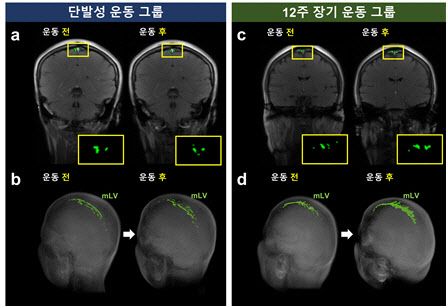

연구팀은 건강한 성인을 대상으로 12주 동안 주 3회 중강도 유산소 운동(실내자전거)을 진행한 뒤 글림파틱 시스템과 뇌막림프 흐름을 측정했다. 그 결과 장기 운동 그룹에서만 뇌척수액과 간질액 교환 경로를 통한 글림파틱 흐름이 증가하고 뇌막 림프관의 크기와 흐름 지표 역시 유의미하게 높아지는 현상을 관찰했다. 반면 단발성으로만 운동한 그룹에서는 이러한 개선 효과가 뚜렷하게 나타나지 않았다.

최승홍 교수는“우리 연구진은 본 연구를 통해 꾸준한 운동 습관이 뇌 건강을 지키는데 필수적이라는 점을 과학적으로 증명하였으며, 운동이 어떻게 뇌 건강을 향상 시키는지에 대한 중요한 연구결과를 제시했다”며“본 연구에 사용된 글림파틱 시스템과 뇌막림프 흐름 MRI 기법을 통해, 실시간으로 뇌 건강을 평가하는데 도움을 줄 수 있다.”고 말했다.